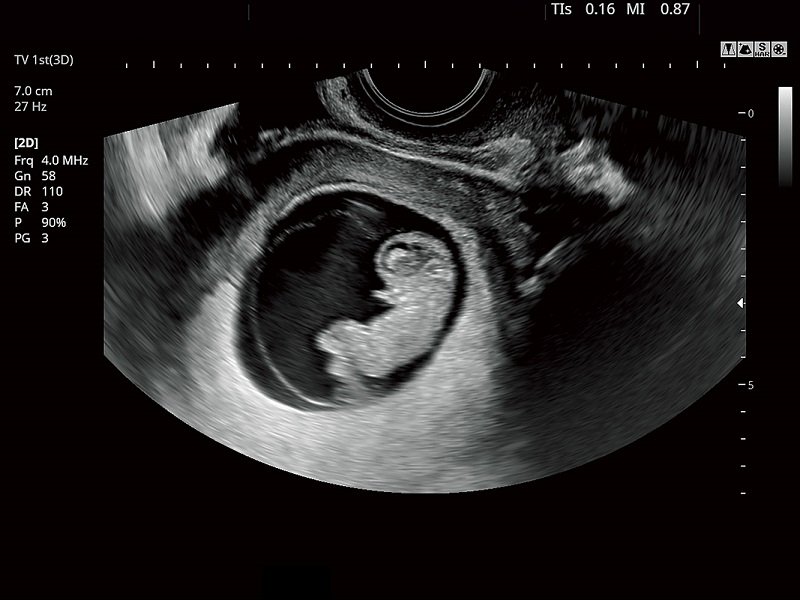

FUTUS features great imaging technologies to support a clear view and confident diagnoses.